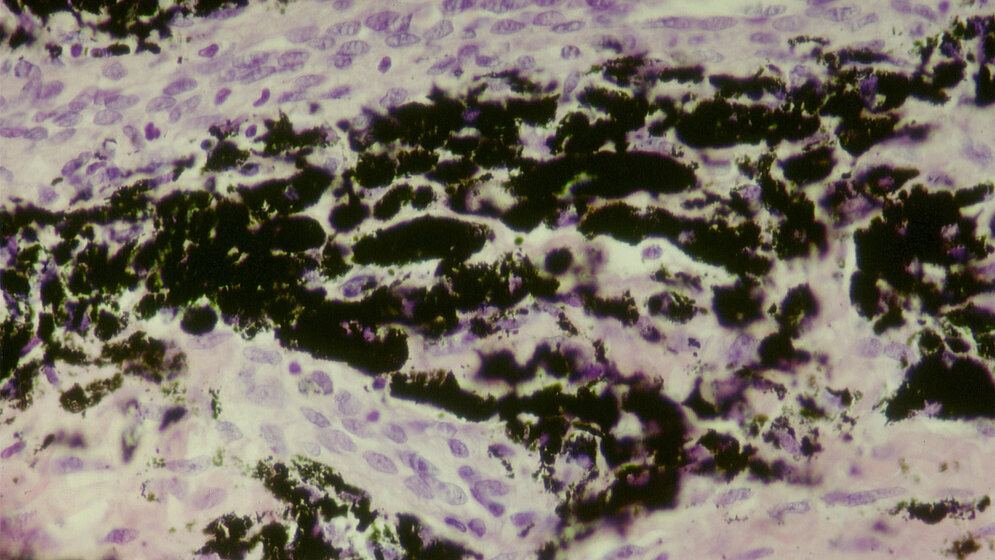

Beim endoprothetischen Ersatz, beispielsweise von Hüft-, Knie- oder Schultergelenken, spielen moderne Materialien eine besondere Rolle. Der Verschleiß muss so gering wie möglich sein, denn die Prothesen sollen schließlich ein Leben lang im Körper bleiben. In der nun ausgezeichneten Arbeit beschäftigte sich die Arbeitsgruppe mit der Analyse eines Einzelfalls. Es handelte sich um ein künstliches Hüftgelenk, das wegen Komplikationen wieder entfernt werden musste. Im umgebenden Gewebe wurden verschiedene Metalle und Legierungen in nanopartikulärer Form nachgewiesen. Mit Elementanalytik bestimmten die Forscher die Identität und Größe der Partikel Tantal, Kobalt, Titan, Chrom, Vanadium, Molybdän und Aluminium. Zusätzlich wurde die Verbreitung im Gewebe untersucht und bewertet.

Fazit: Aus Sicht der beteiligten Wissenschaftlerinnen und Wissenschaftler sollten die Wechselwirkungen zwischen dem Implantat und seinen Verschleiß- und Korrosionsprodukten mit dem menschlichen Gewebe stärker beachtet und überwacht werden, um die Sicherheit von Implantaten zu verbessern.

Janosch Schoon, Anastasia Rakow, Sven Geißler, et al.: Multi-elemental Nanoparticle Exposure after Tantalum Component Failure in Hip Arthroplasty: In-depth Analysis of a Single Case. Nanomedicine: Nanotechnology, Biology and Medicine, November 2017, Volume 13, Issue 8, Pages 2415–2423.